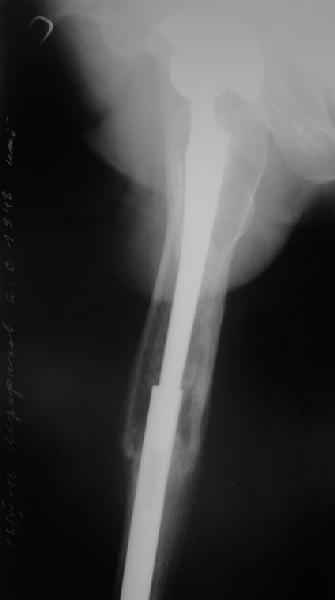

Это сплошной титановый стержень. На дистальном конце отверстия под кондуктор. На другом - канал под ножку глубиной 60 мм, стенки толщиной 2,5-3 мм. И там же продольный пропил, чтобы канал мог адаптироваться к ножке.

Обещанные ранее снимки Заранее спасибо.

Уважаемые коллеги, в данном случае в лечении стандартного перипротезного перелома В2 Ванкуверской классификации (перелом вокруг ножки эндопртеза с потерей стабильности ножки при хорошем - не требующем пластики - качестве кости.Parvizi J, Rapuri VR, Purtill JJ, et al (2004) Treatment protocol for proximal femoral periprosthetic fractures. J Bone Joint Surg Am; 86-A Suppl 2:8-16)с успехом применён оригинальный, но малоизведанный способ лечения подобных повреждений. В результате и последующие рекомендации не могут быть стандартными. В подобных случаях, как это уже дискутировалось год назад, можно было выполнить ревизию длинной ножкой, во многом работающей как интрамедуллярный гводь + плюс кабель/серкляж в проксимальном отделе. Или, оставить имеющуюся ногу плюс длинная пластиа с кабелем/серкляжем, можно разными современными блокированными *примочками*. В таком случае при достижении консолидации пластина удаляется, тк при возникновении в будущем потребности в ревизии имеющийся дополнительный металл и без затруднит непростое вмешательство (кто пробовал, знает о чём я говорю). С длинной ногой, конечно, так же всё понятно. В данном случае мы имеем некую комбинацию, осложнённую отсутствием репозиции и фиксации в прошлом отломков вокруг ножки. Поэтому не каждый в данном случае рискнёт утверждать за счёт какого из компонентов системы - дистального либо проксимального обеспечивается стабильность. А если это и фиксация и за счёт ножки и за счёт гвоздя - каков баланс между данными компонентами в поддержании стабильности ситемы. То есть, я надеюсь, что дистального смещения ножки здесь не будет при условии сохранения как гвоздя, так и блокирующих винтов. При удалении же гвоздя возможна миграция ножки, только винтов - всей системы. Здесь же перелом (надеюсь, его не будет) блокирующих винтов может быть первым свидетельством механического неблагополучия системы... А так, помимо отличного результата этот случай так же косвенно подтверждает известную истину - Эндопротез, к сожалению, требует периодической замены. И выполняя фиксацию перипротезного перелома, а в последующем решая вопрос об удалении имплантатов, мы вынуждены думать и о функции сустава, и о том, как в будущем выполнить ревизию. Если ожидаемая продолжительность жизни пациента заставляет нас об этом думать. С уважением, Андрей